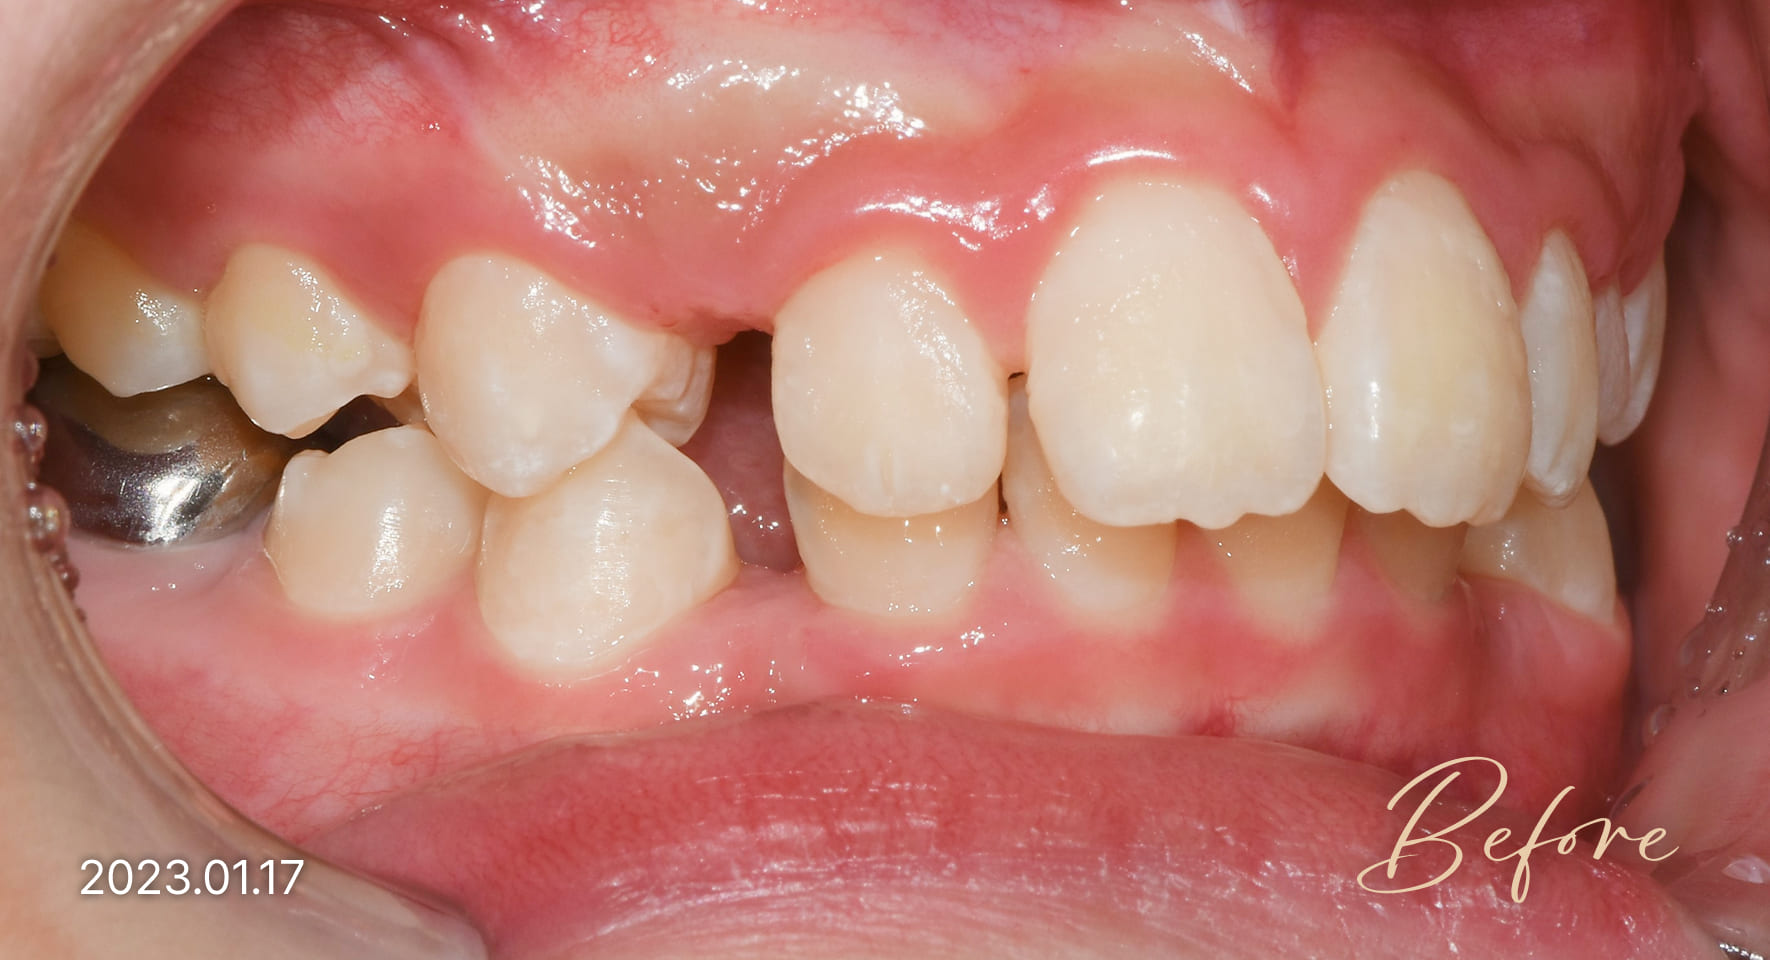

매복치, 덧니 : 10세 전후

매복치와 덧니는 주로 만 10세 전후에 발생하며,

특히 위턱 송곳니에서 흔히 나타납니다.

이를 방치하면 주변 치아와 턱뼈의 성장을

방해할 수 있으므로, 발견 즉시 교정치료를

시작하는 것이 중요합니다.

성장기 교정 치료사례

본 사진은 진심을담은치과교정과 치과의원에서

치료한 환자의 동일 인물 전·후 사진입니다.

개인의 구강 상태 및 관리 방법에 따라 통증 및 잇몸 염증,

치료 전 치료 후